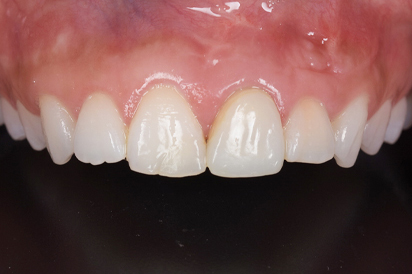

セラミックセット

最終的なジルコニアボンドクラウンをセットしました。すきっ歯がまずなくなりました。また、長かった歯が短くなりましたので本人の希望に沿うことができました。